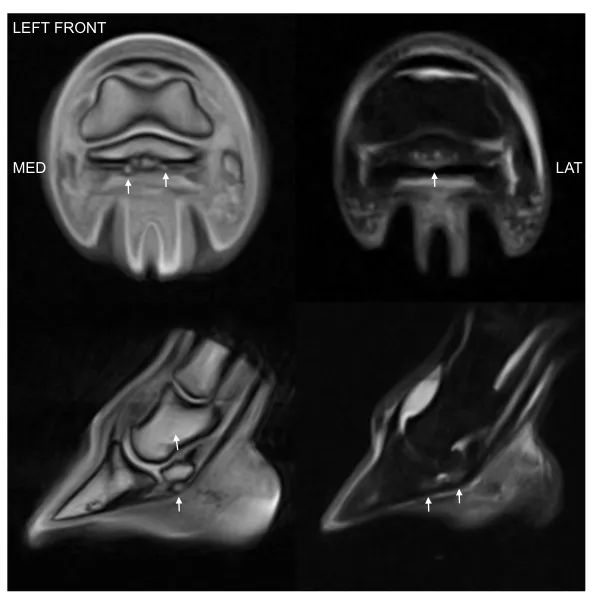

Equine MRI of MD, LLC Photos